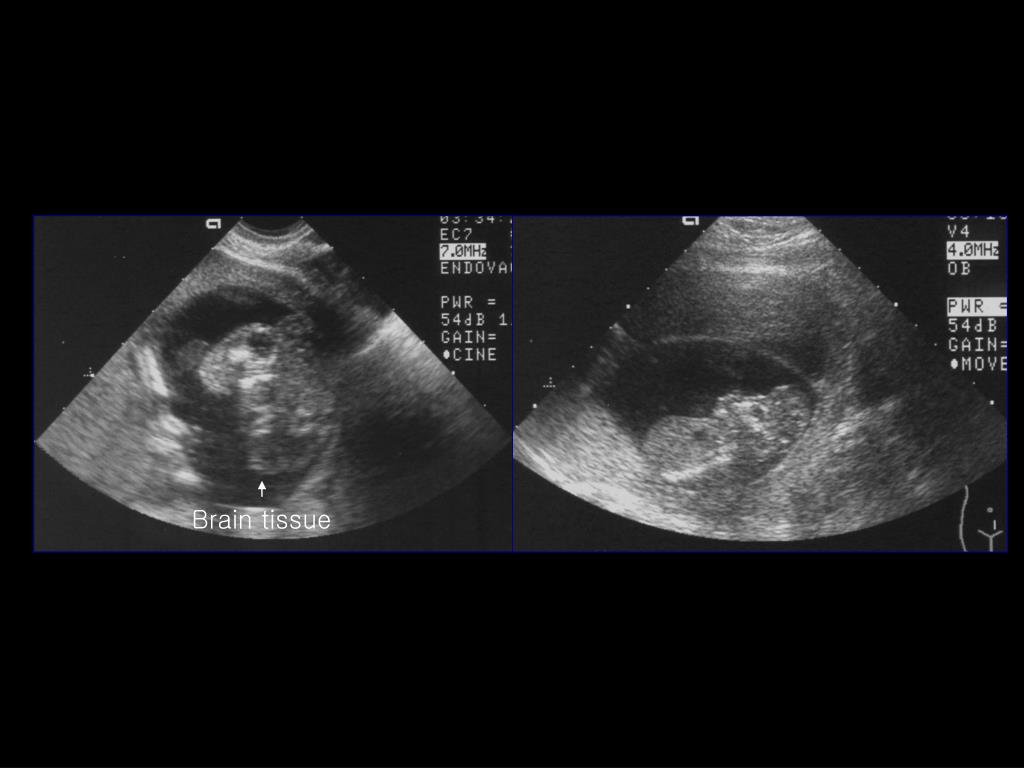

16. Brain tissue

17. Encephalocele • The least common ONTD • Protrusion of intracranial contents through a cranial defects • Site occipital(75%), frontal(13%), parietal • DDx : cystic hygroma